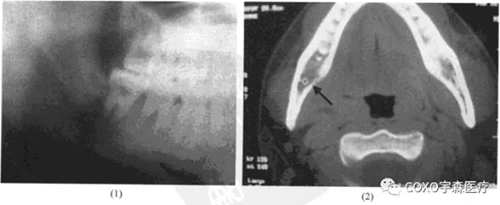

病例:女性,72歲,右下牙齦腫脹3周,有牙痛史,外院拍片診斷為“根尖周囊腫”并行頰側(cè)組織切片檢查,病理診斷為“炎癥性病變”轉(zhuǎn)來我院。

檢查:54]頰側(cè)骨膨隆,頰側(cè)活檢切口無膿性分泌,54]無松動(dòng),無叩痛,6]殘冠、x線片示:654]]冠部均有充填物,4]牙槽骨吸收已近根尖,51]牙槽骨吸收至根長1/2。全景片示:54]根尖陰影,無明顯骨質(zhì)反應(yīng)線(圖13-3),54]電活力測試無反應(yīng)。

局麻下拔除654],見根尖部有大量肉芽組織予以刮除,術(shù)后傷口順利愈合。病理報(bào)告:右下后牙區(qū)根尖周囊腫,伴反應(yīng)性骨質(zhì)增生。

本病例的臨床診斷為根尖周囊腫,似無太大疑問,但X線表現(xiàn)則十分不典型:54]根尖骨質(zhì)呈不規(guī)則、潛穴性吸收,底部幾達(dá)顏孔,更無明顯骨質(zhì)反應(yīng)線。由于54]無明顯松動(dòng)及叩痛,加之頰側(cè)骨質(zhì)膨脹,致使牙體牙髓病醫(yī)師疑為腫瘤,不敢進(jìn)行根管治療術(shù)。手術(shù)結(jié)果證實(shí)仍為根尖周囊腫伴反應(yīng)性骨質(zhì)增生。結(jié)合術(shù)中見病灶區(qū)有大量肉芽組織,說明本病例的炎癥過程可能持續(xù)時(shí)間較長,程度較重,致使 線片表現(xiàn)呈不典型性。本例的經(jīng)驗(yàn)是:應(yīng)牢記根尖周囊腫還有不典型表現(xiàn)者,臨床應(yīng)綜合各方面的因素考慮,方能更進(jìn)一步提高臨床診斷水平。